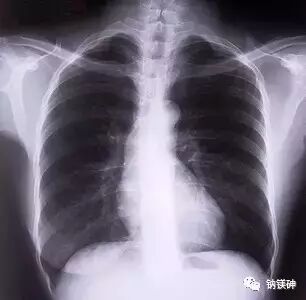

呼吸机的禁忌症是:

(1)气胸与纵隔气肿未行引流者。

(2)大量胸腔积液。

(3)巨大肺大泡。

(4)低血容量休克未纠正者。

(5)急性心梗伴有心功能不全者。但气胸、支气管胸膜瘘、急性心肌梗塞、心功能不全者,必要时可使用高频通气。